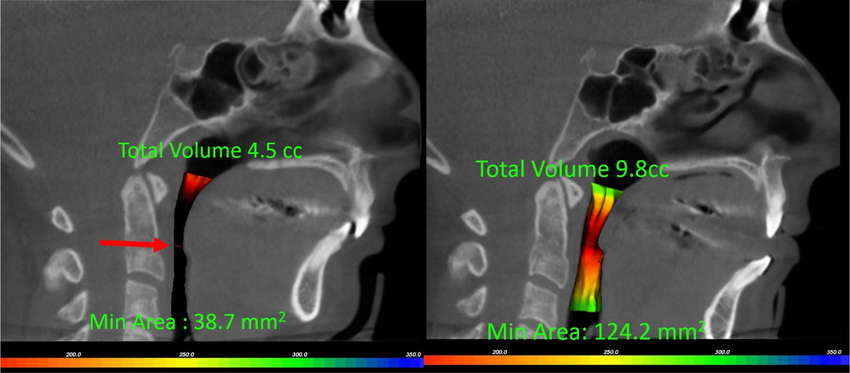

Airway centered dentistry is looking at teeth and the oral system holistically and understanding how the position of the teeth and jaw could affect airway, breathing, and sleep- how it could potentially impact overall health system in one's body.

Upper airway assessment is essential in orthodontics because of the close inter-relation between the correct respiratory function and the normal development of craniofacial structures and health, and greatly improve their quality of life.

This includes initial analysis of the patient’s airway, usually followed by a removable functional appliance therapy, and braces if required.

Our approach includes airway-centered orthodontics, which recognises the importance of airway health in orthodontic care. By evaluating the patient’s airway during the initial assessment, our orthodontist specialists can recommend treatments that may involve functional appliances or braces to improve overall breathing and comfort.